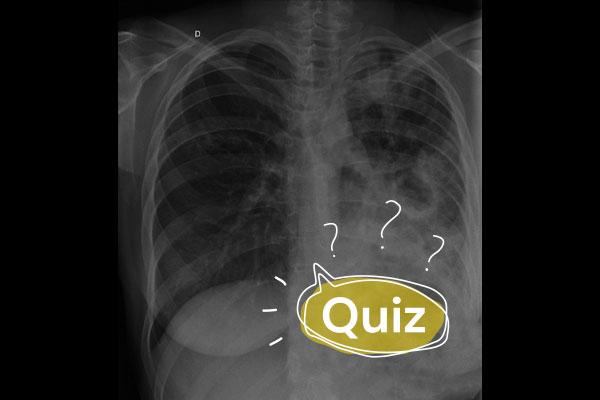

Sintomas catarrais evoluiram há duas semanas com piora da tosse, expectoração mucoide, febre diária de 39ºC e outros sintomas.